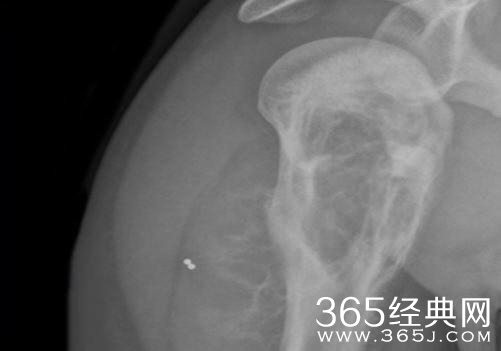

人气演员刘亚仁在5月22日接受的第5次体检中,被判定罹患骨癌,最终免服兵役。

面临服役的刘亚仁在治疗过程中先后接受了5次体检,最终被判定免服兵役。